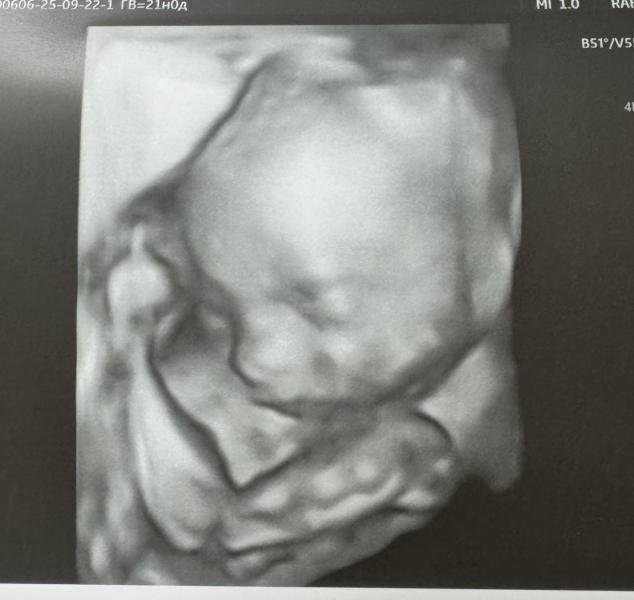

Вот и прошел 2й скрининг! Наверное, пока это самый эмоциональный этап!🥲

С малышом всё замечательно, размеры соответствуют 20н5д (на 1 день отстаем, но это вообще не критично!). Все УЗИ вошкался и пинался😂 видимо не давали парню спокойно отдохнуть. По итогу перевернулся на 180 градусов и повернулся спиной! Весим 353г💪

Дал пофоткать личико😍